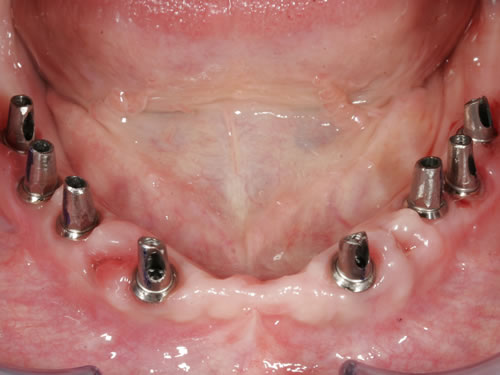

Abb. 3.5: Kugelknöpfe im Mund.

Abb. 3.6: Prothesenansicht von unten mit eingearbeiteten Sekundärteilen.

Diese Beispiele ließen sich endlos fortführen. Sie zeigen die Probleme bei der Versorgung zahnloser Kiefer, wie sie immer wieder geschildert werden. Mit Hilfe sehr einfacher Maßnahmen kann durch die Einpflanzung künstlicher Zahnwurzeln eine instabile Prothese soweit befestigt werden, dass die Kau- und Sprechfunktion wieder hergestellt ist. Manchmal kann die alte Prothese weiterverwendet werden, in dem man in die Prothesenbasis Sekundärteile einarbeitet, die für Halt sorgen (Abb. 3.5, 3.6). Bei aufwendigeren Steg- oder Teleskoparbeiten muss auch der Zahnersatz der auf den Implantaten fixiert wird neu angefertigt werden. Diese Arbeiten werden dann brückenartig und sehr grazil gestaltet. (Abb. 3.7 bis 3.12).